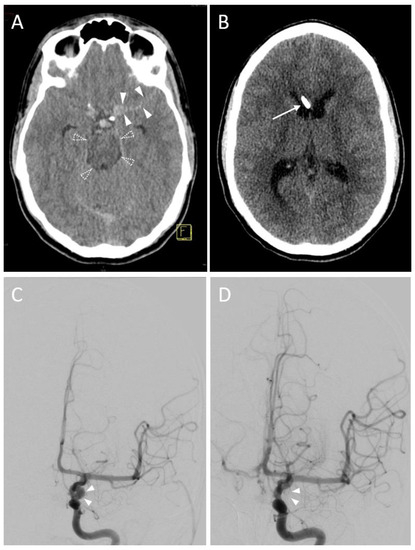

3.2.3. Accuracy

| EVD position in 1st control CT scan | |

| Kakarla I | 28 (77.8) * |

| Kakarla II | 8 (22.2) * |

| Final EVD position | |

| Kakarla I | 35 (97.2) * |

| Kakarla II | 1 (2.8) * |